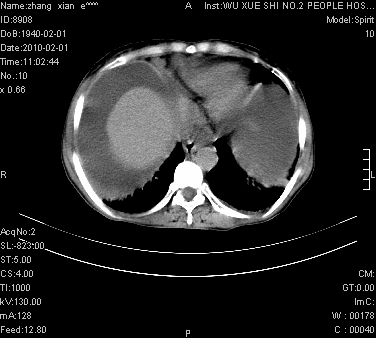

标题: CT24434:70岁 女 腹胀,腹水原因待查 [打印本页]

标题: CT24434:70岁 女 腹胀,腹水原因待查

大量腹水,脾脏囊性占位,子宫颈占位,右侧腹股沟淋巴结肿大,建议+c,先查妇科。

腹盆腔大量积液,子宫增大,子宫颈增大外形不规则,内见低密度影,膀胱后壁显示不清,右腹股沟肿大淋巴结,脾脏囊性占位,子宫颈占位,子宫颈癌?建议增强。

子宫、宫颈占位?转移性腹水?肝性腹水?脾脏囊性占位,囊肿?血管瘤?淋巴瘤?

考虑:1、腹膜转移,大量腹水;

2、脾占位性病变;

3、左侧卵巢占位性病变,建议增强进一步检查。

大量腹水,右肾、脾囊肿可能性大          考虑左侧附件区占位,建议增强